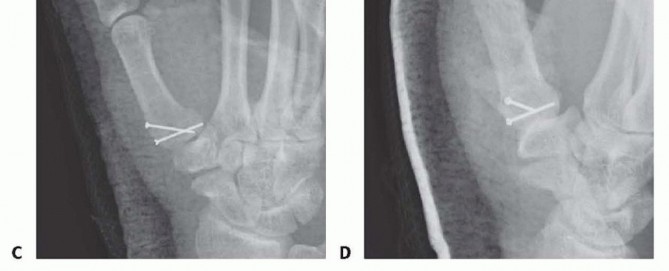

Fixation Strategies for Rolando and Comminuted Patterns

Rolando fractures present a significantly higher degree of complexity. The classical Y or T pattern often precludes simple lag screw fixation. In these instances, mini-fragment plating is the gold standard. T-plates or specialized condylar plates are contoured to fit the complex geometry of the metacarpal base. The articular fragments are first reduced and provisionally pinned, essentially converting the complex intra-articular fracture into a simpler two-part extra-articular fracture. The plate is then applied to buttress the articular fragments and bridge the metaphyseal comminution to the diaphysis.

Image

In cases of severe, non-reconstructable articular comminution where internal fixation is impossible, joint-spanning external fixation combined with limited internal fixation (K-wires) is utilized. The external fixator relies on the principle of ligamentotaxis to restore length and align the articular fragments. Pins are placed in the trapezium (or radius) and the thumb metacarpal shaft, distracting the joint to allow for secondary bone healing while preventing collapse.